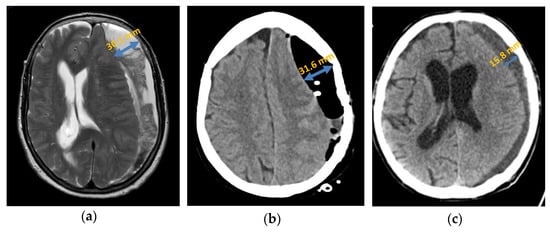

Axial computed tomography of chronic subdural haematoma: (a) preoperative presentation; (b) postoperative subdural air accumulation; (c) recurrence of chronic subdural haematoma.

Figure 4.

Axial presentation chronic subdural haematoma: (a) preoperative septation in axial plane in MRI; (b) postoperative subdural air accumulation in CT; (c) recurrence of chronic subdural haematoma in CT.